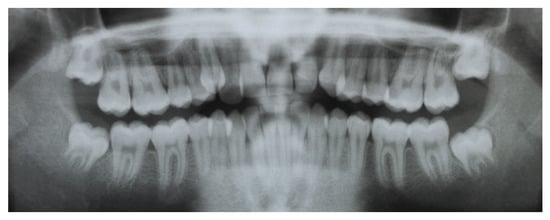

2.5. Results